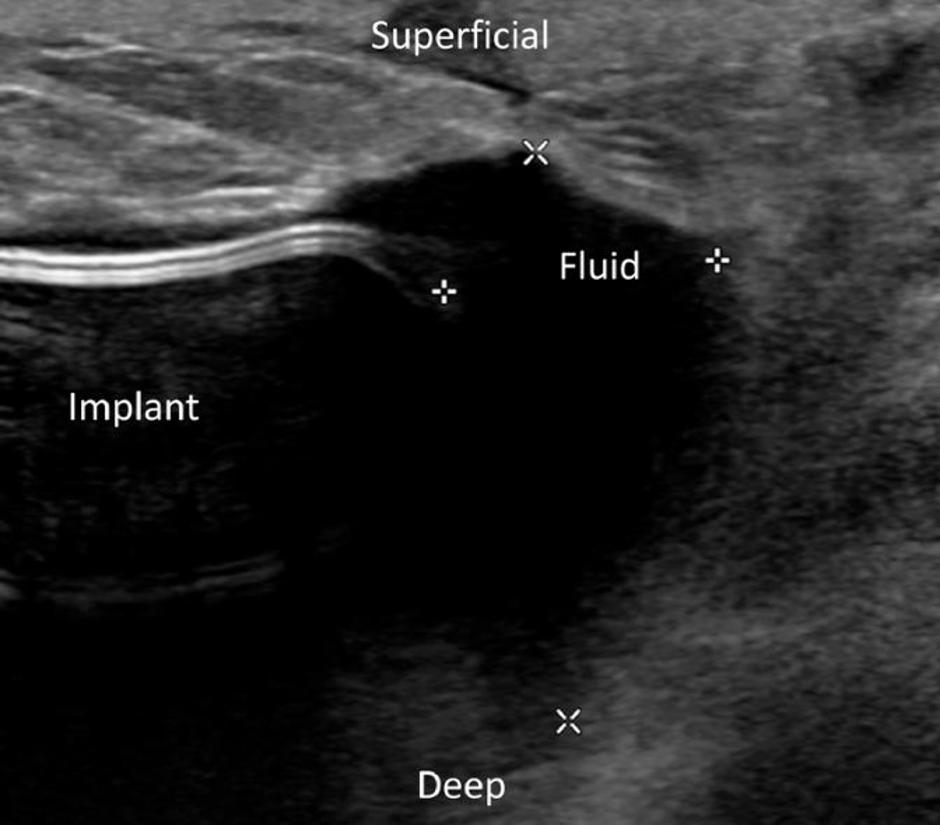

Avtorji poročila navajajo, da je v bila med ultrazvokom zaznana "majhna količina homogene tekočine" okoli desnega implanta. Dobila je predpisane antibiotike, vendar se je bolečina le še stopnjevala, povzema Fox News.

"Odpeljali so jo v operacijsko sobo, kjer so ji prerezali absces in odstranili vsadek, so zapisali avtorji poročila tega nenavadnega medicinskega primera. Poznejša analiza je pokazala, da je tekočina okoli implantanta vsebovala kulture bakterije salmonella, česar v medicinski literaturi še niso zaznali. Ženski so svetovali, da lahko šele štiri mesece po prenehanju jemanja antibiotikov dobi novi vsadek.